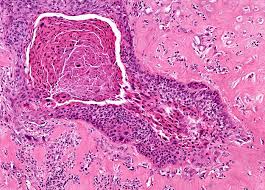

Laryngeal Cancer Johns Hopkins Medicine from www.hopkinsmedicine.org Laryngeal cancer usually occurs in smokers, although it's not quite as common as lung cancer. A cancerous (malignant) tumour is a group of cancer cells that can grow into and destroy nearby tissue. Laryngeal cancer is a type of cancer that affects the larynx (voice box). The larynx is located in the anterior neck at the level of c3 to c6. The larynx is the voice box located at the top of the windpipe (trachea). In workshops from the centennial conference on laryngeal cancer (alberti, p. Laryngeal or larynx cancer is one of the type of cancers that can metastasize and at which stage can't be cured anymore. Laryngeal cancer symptoms include voice changes, such as hoarseness, and a sore throat or cough that doesn't go away.

Mouth Pharynx Larynx Cancers Wcrf International from www.wcrf.org What are the signs of throat (laryngeal) cancer? Find out how this condition affects us, and learn. Treatment may include surgery to remove part or all of the larynx, called a laryngectomy. Tepper je, foote rl, michalski jm, eds. The vast majority of applicable cases are squamous cell carcinomas, but other epithelial tumors t3: Cancer can develop in any part of the larynx. What is cancer of larynx or laryngeal cancer? Laryngeal cancer symptoms include voice changes, such as hoarseness, and a sore throat or cough that doesn't go away.